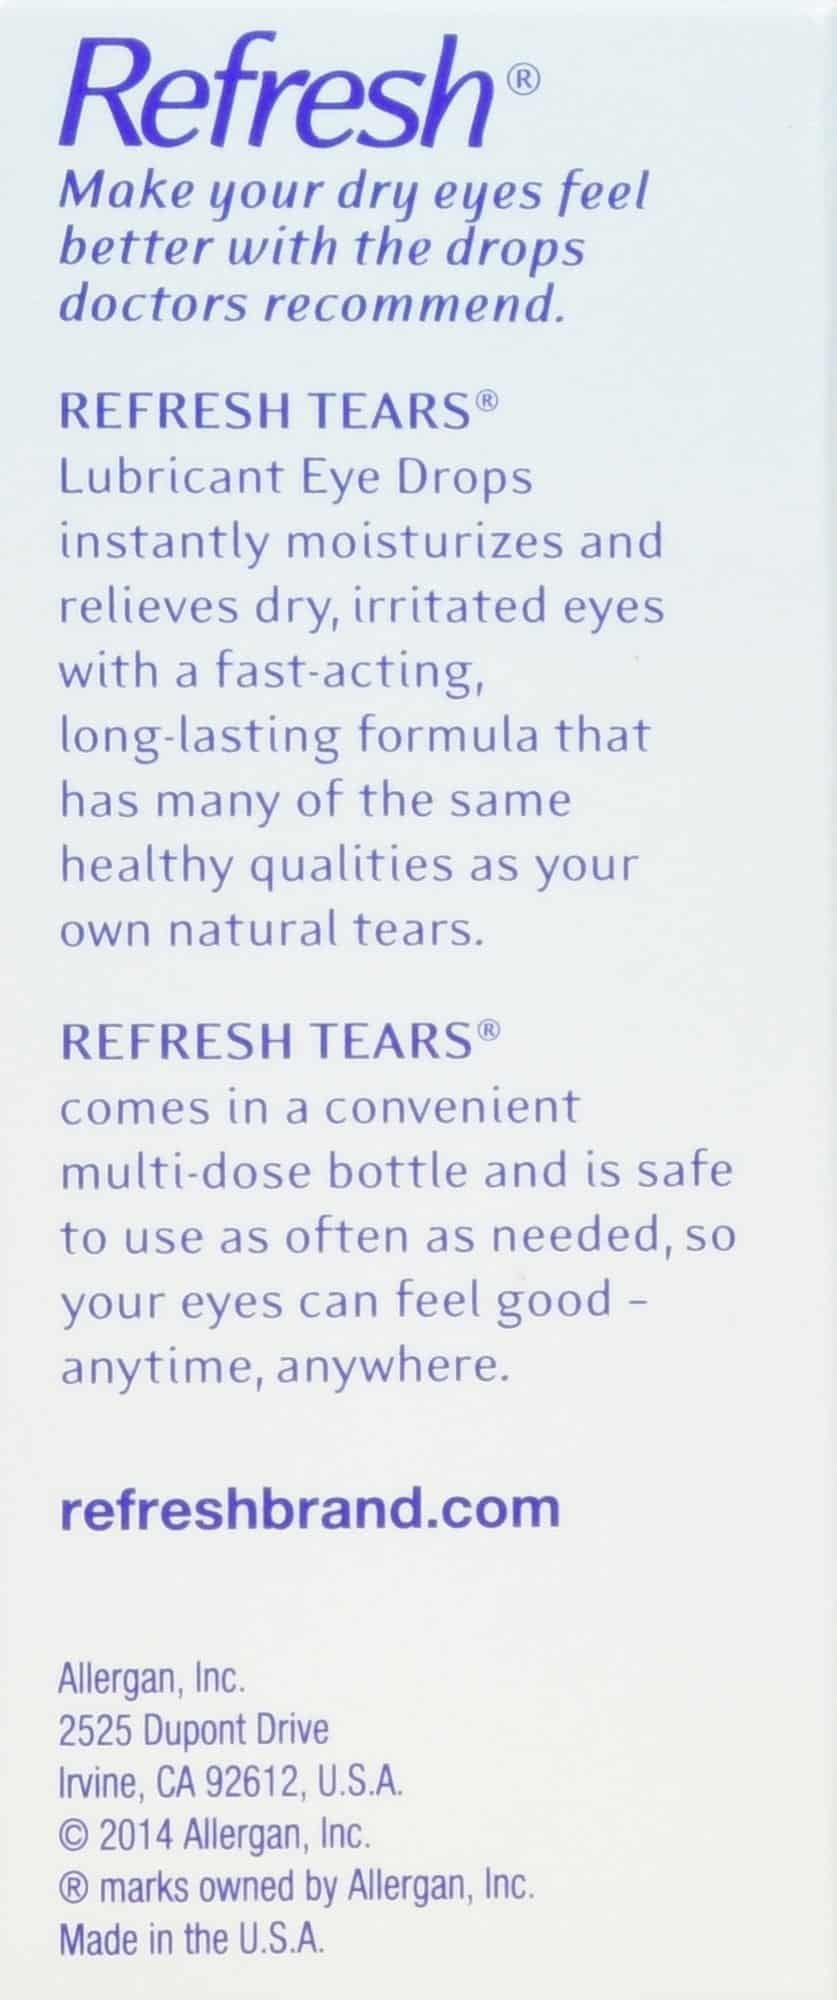

Original price was: ₹14,184.₹10,507Current price is: ₹10,507.Refresh Multi-Pack 65 ml Refresh Tears, 2.17 FlOZ

2.17 fl oz. Refresh Tears Lubricant Eye Drops, Moisture Drops for Dry Eyes. 4- .5 fl oz. bottles and 1- .17 fl oz bottle